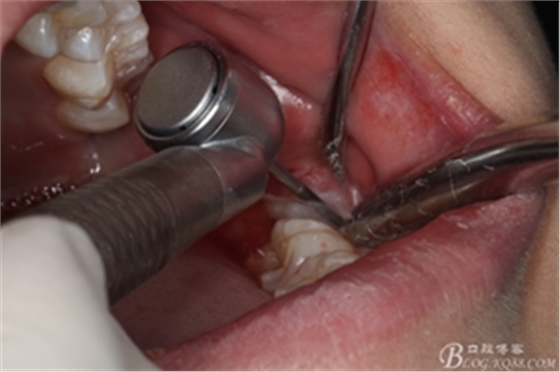

圖10. 翻開(kāi)瓣。38牙冠還有部分骨質(zhì)覆蓋,遂用高速牙鉆去骨

圖11.去骨---暴露出38的牙冠最大周徑

圖12.高速牙鉆分牙